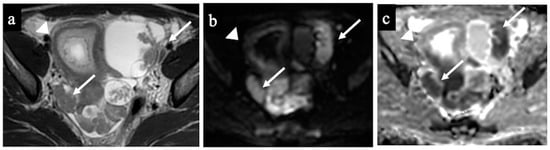

Figure 5 and Figure 6 show two cases of correct diagnoses made by the expert and the non-expert radiologists: one case of a struma ovarii, a multilocular cystic mass without solid tissue that was correctly considered benign/NCMS 2 (true negative), and a case of a low-grade ovarian serous cancer with papillary projections and mural nodules (solid tissue) correctly classified as malignant/score 4 (true positive).

Figure 5. Struma Ovarii. MR images of a 34-year-old woman—16 weeks pregnant—with an indeterminate adnexal mass accidentally discovered at first trimester US. The axial T1 with fat saturation (a) and coronal (b) and sagittal T2-WI (c) images show a multilocular cystic mass with different signal intensities within the loculi. Some loculi have a very low signal intensity on the T2-WI (white arrow in image (b)) corresponding to colloid. No solid tissue is seen within the lesion; thus, it was correctly considered as benign/NCMS 2 according to both readers (true negative).

Figure 6. Low-grade ovarian serous cancer. MR images of a 33-year-old woman—7 weeks pregnant—with bilateral indeterminate adnexal lesions discovered at the 6-week US. The axial T2-WI (a), DWI (b) and ADC-map (c) show bilateral adnexal masses with papillary projections and mural nodules (solid tissue) within the lesions (arrows). Solid tissue has an intermediate signal on T2-WIs and corresponding true diffusion restriction. Free pelvic fluid is seen in the pouch of Douglas. No carcinosis was present, so the lesions were correctly classified as malignant/score 4 by both the readers (true positive). Note the gestational sac in the uterine cavity (arrowhead).